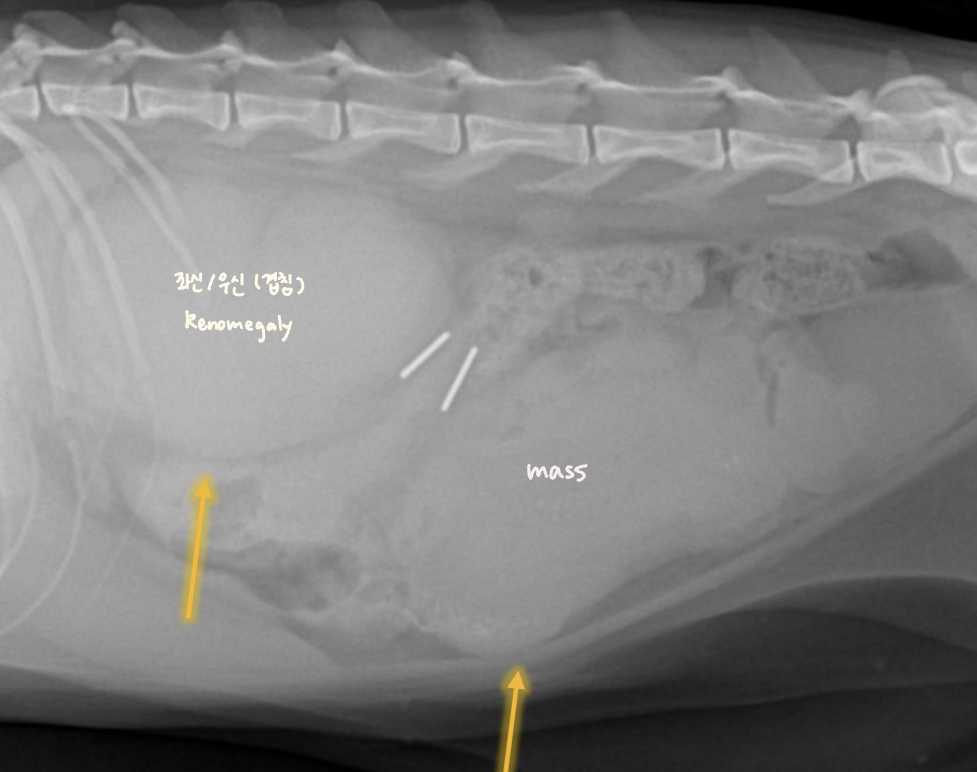

Fluid or Mass

- Fluid : ์ธ์ธก์์์ ์ค์์ผ๋ก ๋ชจ์. diffuseํ ์ฐ๋ถ์กฐ์ง ๋ฐ๋.

- Mass : ์๋ฆฌ๋ฅผ ์ฐจ์งํจ โ ์ฅ์ ๋ฐ์ด๋. & ์ข ์์ด ์ปค์ง๋ฉด์ ์ถํ์ ์ ๋ฐ.